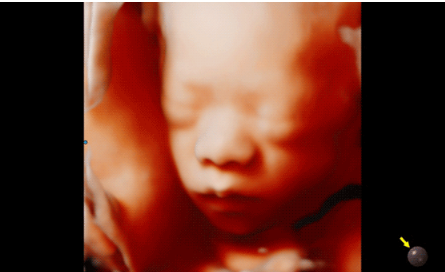

3D/4D成像方面,Hera i 10通過結(jié)合先進的圖像渲染技術(shù),著重加強了邊緣和小結(jié)構(gòu)的可視化能力。